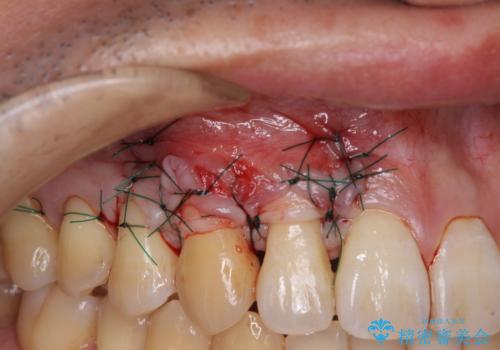

八重歯の歯根が見えている点も気になっているので、矯正歯科治療後に歯肉移植による根面被覆を行うこととしました。

矯正治療により元々気になっていた八重歯と、反対咬合が改善された歯の2本に対して根面被覆を行い、審美面の改善も達成しました。

- 外科手術のため、術後に痛みや腫れ、違和感を伴います